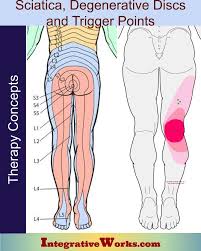

Download Sciatic nerve pain pictures